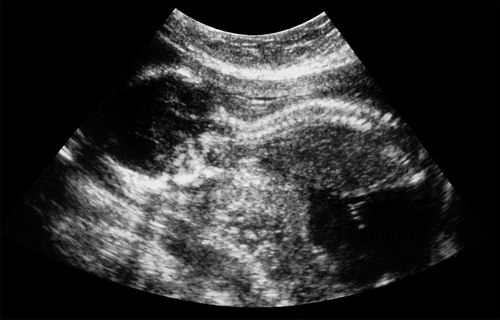

脊柱裂是一种妊娠期间胎儿脊髓未完全闭合的疾病,全球新生儿的发病率低于千分之一,但在低收入国家发病率较高。其中最严重的一种类型是脊髓脊膜膨出,可能导致大脑积液过多、潜在脑损伤、瘫痪以及膀胱和肠道控制障碍。

6名孕妇在妊娠24至25周时接受了手术。手术过程中,研究人员将从捐赠的胎盘中产生的干细胞直接植入胎儿暴露的脊髓。研究人员称,手术全程未出现并发症,孕妇在妊娠34周左右生产,新生儿未见感染、脑脊液渗漏或肿瘤生长迹象。Farmer表示,有人曾担心干细胞可能会癌变。同时,有迹象表明,所有新生儿脊髓脊膜膨出的一种并发症——后脑疝都已得到逆转。后脑疝是指大脑后部下陷至颈部,阻塞脑脊液的循环。